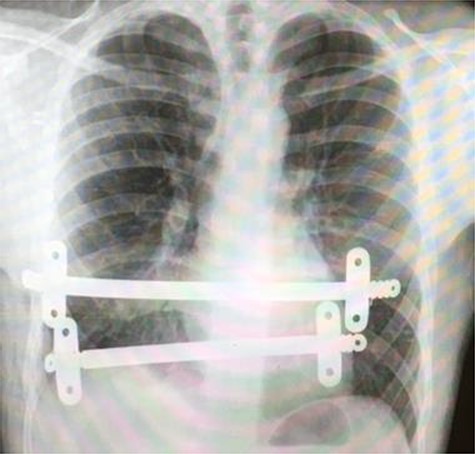

Superior lateral intraoperative view of the laparotomy used to access and remove the second migrated bar.

Our patient was followed up annually. After two and half years, he developed a right-sided wound infection, initially treated with antibiotics. It was decided to remove the bar for prevention of recurrent infection. The chest X-ray showed migration of the lower-placed bar (Fig. 2). The upper bar and associated stabilizers were removed through the bilateral small incisions without any complication; however, the lower bar was not palpable. Therefore, a left-side thoracotomy was performed; however, the bar was not found in the chest. The incision was extended to a midline laparotomy (Fig. 3). This revealed an erosion of the bar in to the stomach after passing over the left lobe of the liver (Fig. 4). The bar and stabilizers were completely removed, and the hole in the stomach was closed directly with sutures. The patient was discharged home without any further complication after successful recovery.